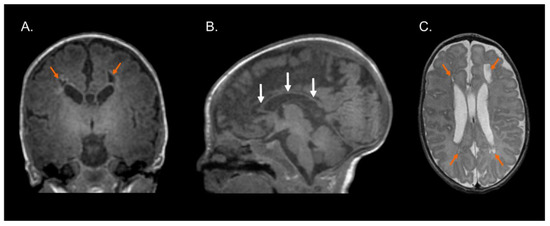

Figure 1, Figure 2 and Figure 3 show the MRI of three infants at the beginning of Katona’s treatment.

Figure 2.

Structural MRI at term-equivalent age of preterm infant (born at 29 gestational weeks) with cystic-PVL. T1-weighted coronal (A) and sagittal (B) images and T2-weighted axial image (C) showing bilateral cystic white matter lesions (orange arrows), global thinning of the corpus callosum (white arrows), dilated lateral ventricles secondary to cerebral white matter loss, and myelination process delay. Images in radiological convention.